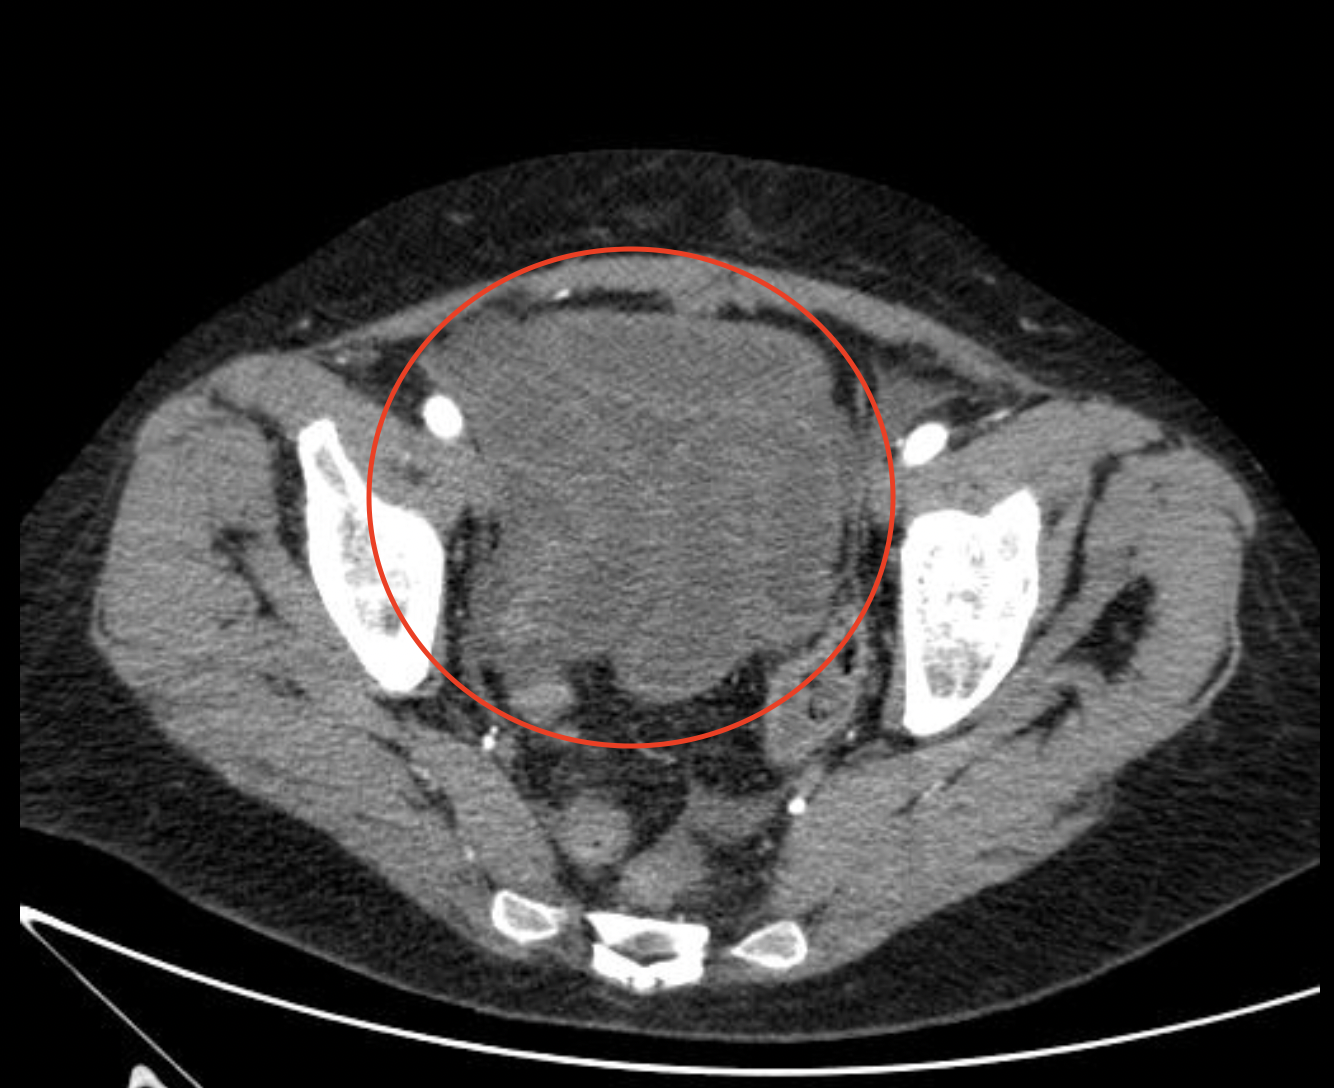

Заворот кишок